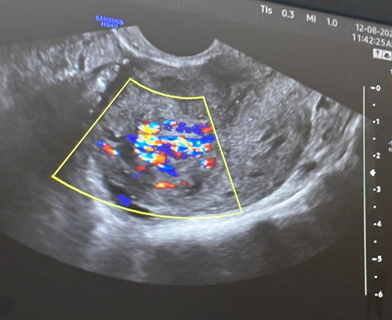

A urine pregnancy test turned out to be negative. On sonographic evaluation, the uterus was 5.4cmX5.1cmX7.3cm (mildly bulky) with heterogeneous echotexture with echogenic areas measuring 2.1cm X 1.87cm X cm2.1 cm with few anechoic areas within and increased vascularity (PSV: 64 cm/sec) within the myometrium which extended into the endometrial cavity. Multiple dilated veins were seen in bilateral adnexa. This led to a differential of uterus arteriovenous malformation (AVM) versus grade 3 retained products of conceptus (RPOC). Considering the high PSV and the type of vascular flow within the myometrium, the diagnosis was more inclined towards AVM (Figure 1).

Figure 1 Doppler flow showing increased vascularity within the uterine AVM.